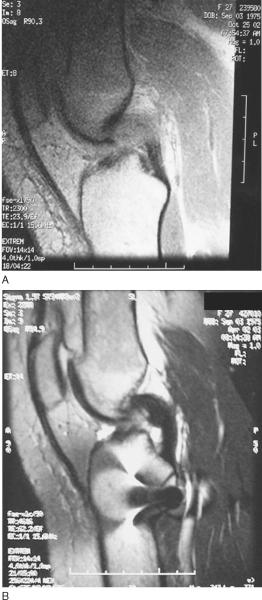

PCL injuries occur with a posteriorly directed blow to the proximal tibia, often from a dashboard or hyperextension injury to the knee. When the mechanism of injury involves a direct blow to the anterior tibia, the foot position at the time of contact plays a role in the injury pattern; ankle plantar flexion is associated with PCL injury, and ankle dorsiflexion is associated with patellofemoral injury (

Fig. 68-3

). Patients often suspect an injury to the knee, although the presentation is much less dramatic than with ACL injuries. Most isolated PCL injuries are grade I or grade II and may be treated nonoperatively with emphasis on regaining of full range of motion and quadriceps rehabilitation to counteract the tendency toward posterior tibial subluxation. In many circumstances, the PCL may actually “heal” as seen on magnetic resonance imaging (

Fig. 68-4

). Debate continues about persistent objective laxity in these “healed” PCL tears; however, lower grade, isolated PCL injuries are still treated nonoperatively. [17] [18] Grade III PCL injuries are rare in isolation and are most frequently seen with loss of secondary restraints and concomitant posterolateral knee injury. It is extremely important that PCL injuries associated with lateral side injuries are identified because this will affect both the treatment and results of PCL injury and reconstruction (